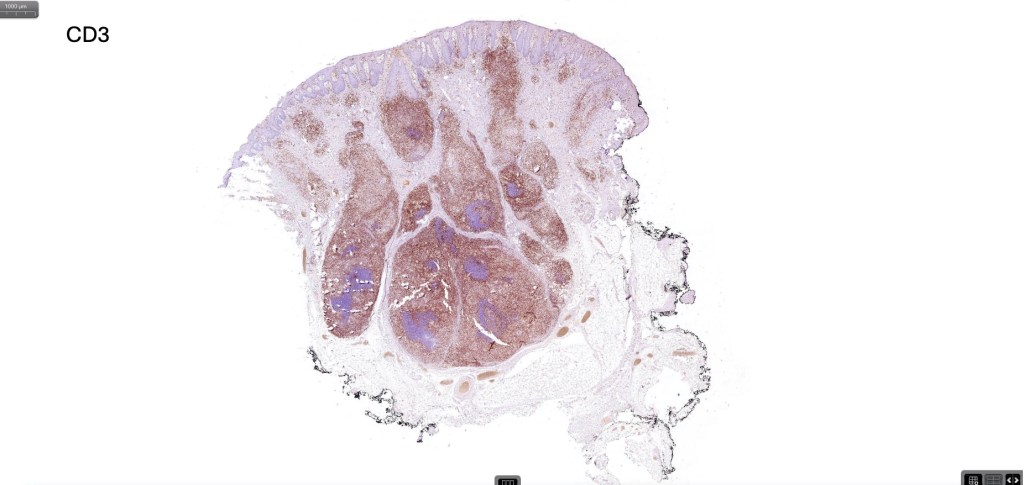

Histological features

•Follicular infiltration by atypical lymphocytes & Sézary cells